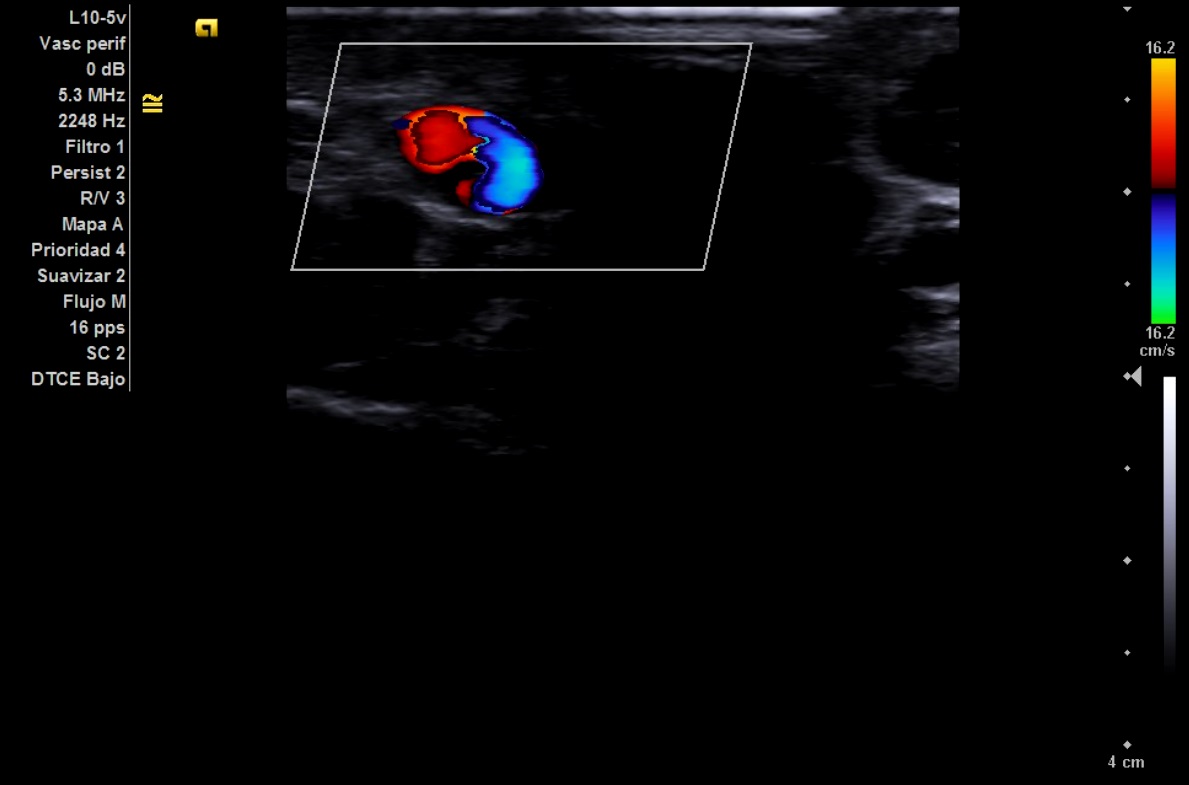

Imagen 3 y 4: Corte transversal. Signo del Yin Yang.

Secuencia doppler en la que podemos ver dos flujos en el interior de la lesión, dando lugar al conocido como signo del Yin Yang.